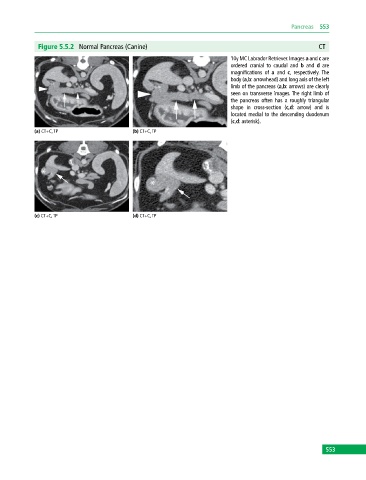

Figure 5.5.2 Normal Pancreas (Canine) CT

10y MC Labrador Retriever. Images a and c are

ordered cranial to caudal and b and d are

magnifications of a and c, respectively. The

body (a,b: arrowhead) and long axis of the left

limb of the pancreas (a,b: arrows) are clearly

seen on transverse images. The right limb of

the pancreas often has a roughly triangular

shape in cross‐section (c,d: arrow) and is

located medial to the descending duodenum

(c,d: asterisk).

(a) CT+C, TP (b) CT+C, TP

(c) CT+C, TP (d) CT+C, TP